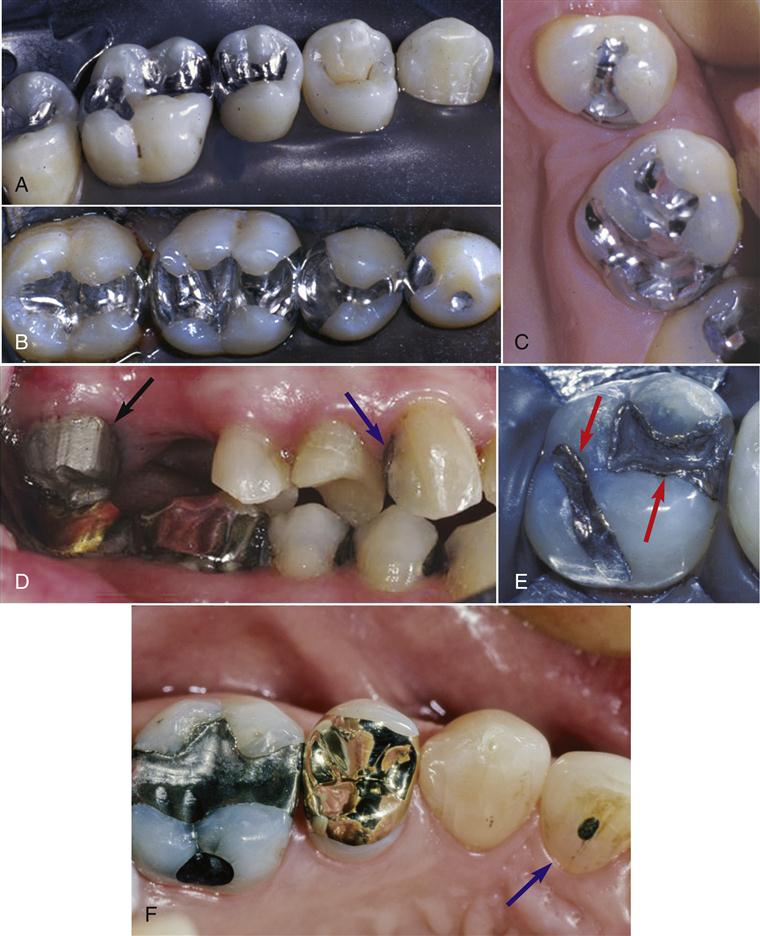

(1)金属嵌体:有贵金属及非贵金属合金嵌体。金合金化学性能稳定,有良好的延展性能和机械性能,是制作后牙嵌体理想的传统修复材料(彩图3—10)。